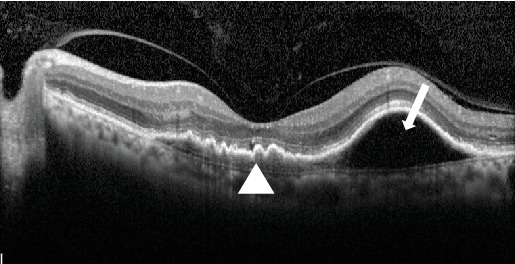

Purpose: The aim of this study is to report a unique case where brolucizumab administration resolved multilayered pigment epithelial detachment (MLPED) lamellae. Observations: An 80-year-old gentleman with polypoidal choroidal vasculopathy developed MLPED from long-term ranibizumab treatment. Switching to brolucizumab led to visual acuity improvement after three doses and complete resolution of fluid, reduced choroidal thickness, and MLPED collapse. Notably, the patient experienced a recurrence of MLPED, which again resolved after the fourth dose of brolucizumab. Conclusions and Importance: This case underscores the effectiveness of brolucizumab in resolving MLPED lamellae, a previously unreported phenomenon. Furthermore, it highlights the potential for visual acuity improvement despite MLPED resolution. Brolucizumab's mechanism of action, including its potent antivascular endothelial growth factor properties and enhanced tissue penetration, may contribute to the collapse of MLPED by modulating subretinal pigment epithelial fluid dynamics. Further research into molecular pathways, cellular interactions, and safety profiles is warranted to optimize the therapeutic role of brolucizumab.

Abstract Image